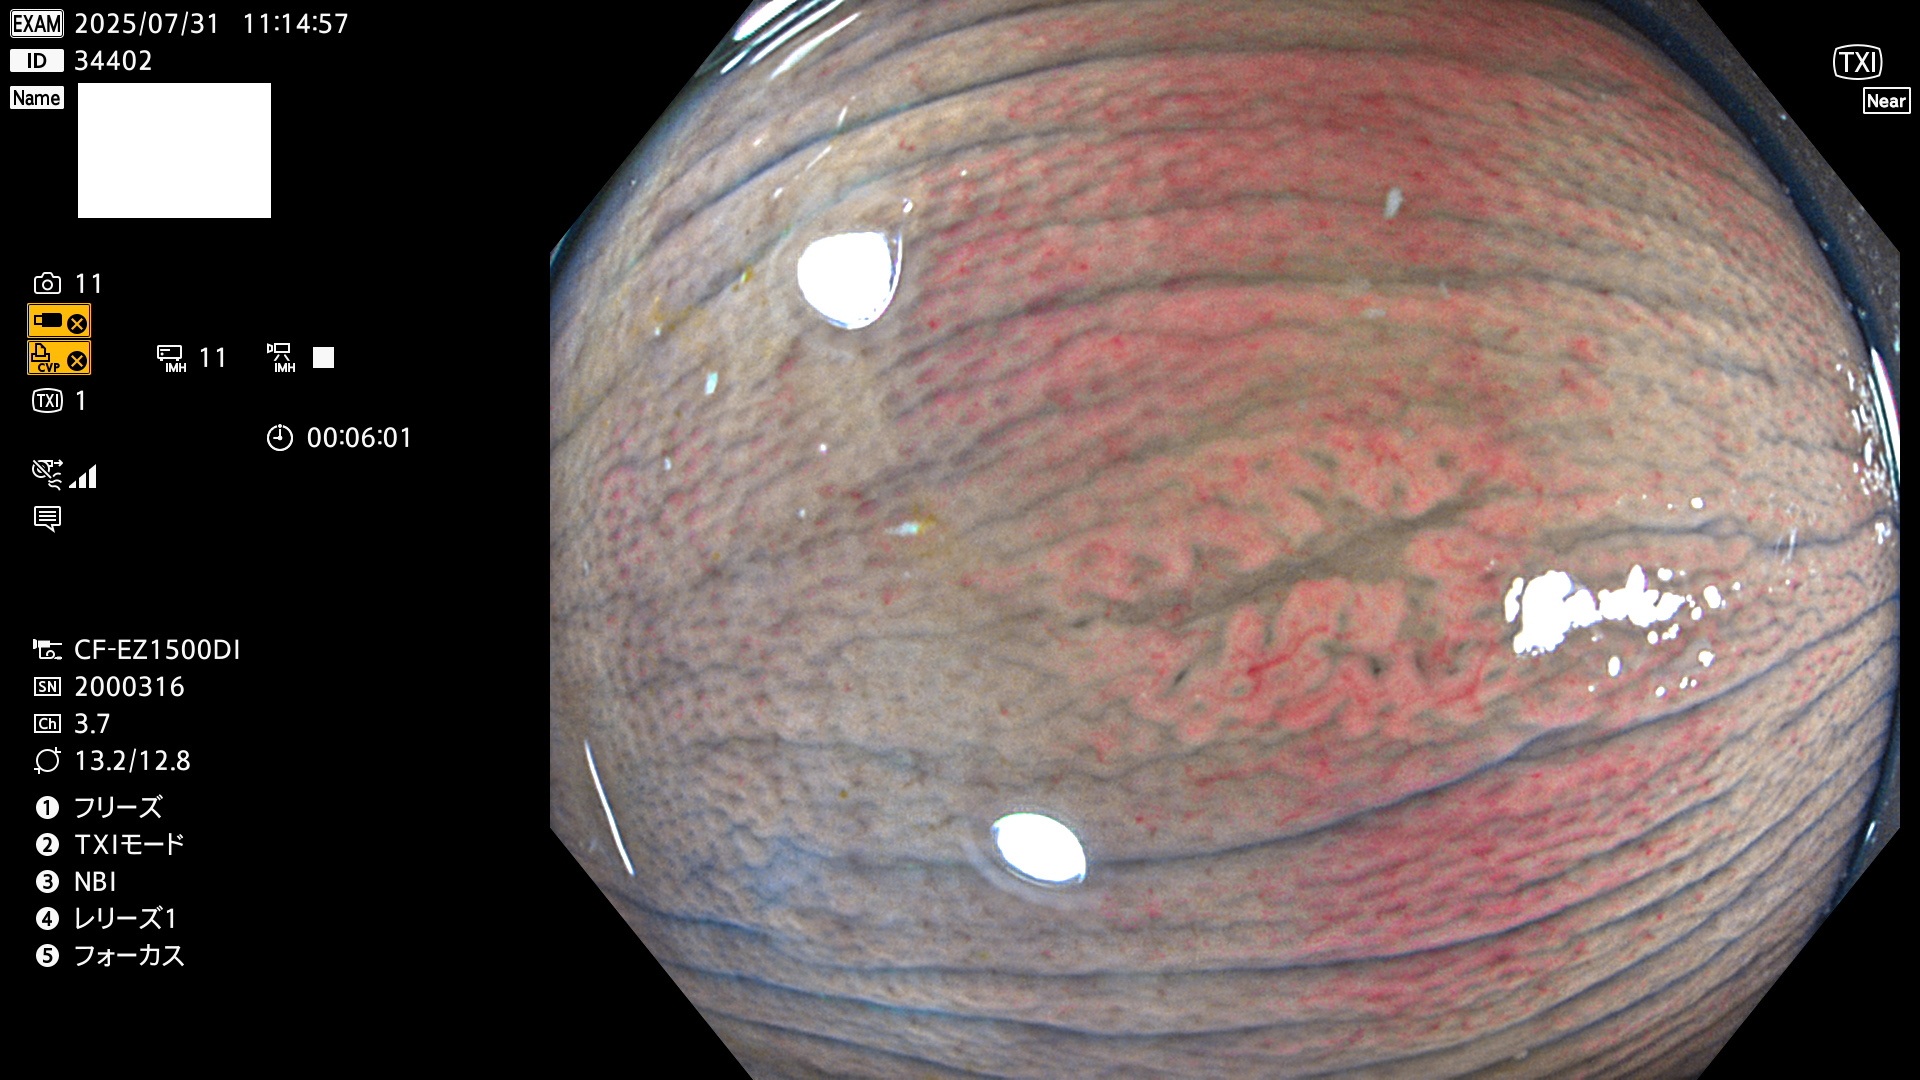

2025年7月31日〜8月3日の4日間(35件)5個 (Uc_ADR=5個/35人=14%)